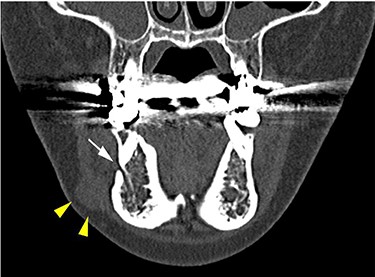

She had a 15-mm, painless, non-pitting and indurated mass at the right mandibular margin (Fig. 1). Oral examination revealed no mucosal abnormalities or swelling. The mass was difficult to palpate from the oral side due to the presence of buccal frenulum on the mucosa over the mass. Magnetic resonance imaging (MRI) revealed a 15-mm nodule with a clear border at the right mandibular margin, with low and high signal intensities on T1- and T2-weighted images, respectively (Fig. 2). Computed tomography (CT) revealed a 15-mm low-density nodule in the right mandibular margin. Calcification, bone invasion or lymph node enlargement were not observed (Fig. 3). The mass was radiologically diagnosed as an epidermoid cyst. The differential diagnoses were schwannoma, neurofibromatosis, pleomorphic adenoma and a powdery mass; however, schwannoma was considered to be most likely.

CT findings of a coronal section; yellow arrowheads indicate the schwannoma; the white arrow indicates the mental foramen.